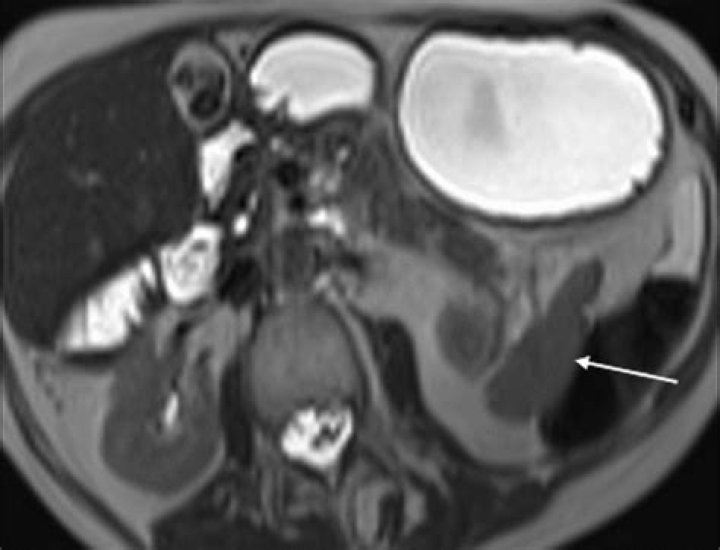

Context Celiac disease is one of the most common lifelong disorders. Non-Hodgkin lymphoma is a possible complication of celiac disease and may lead to a large portion of lymphoma cases.